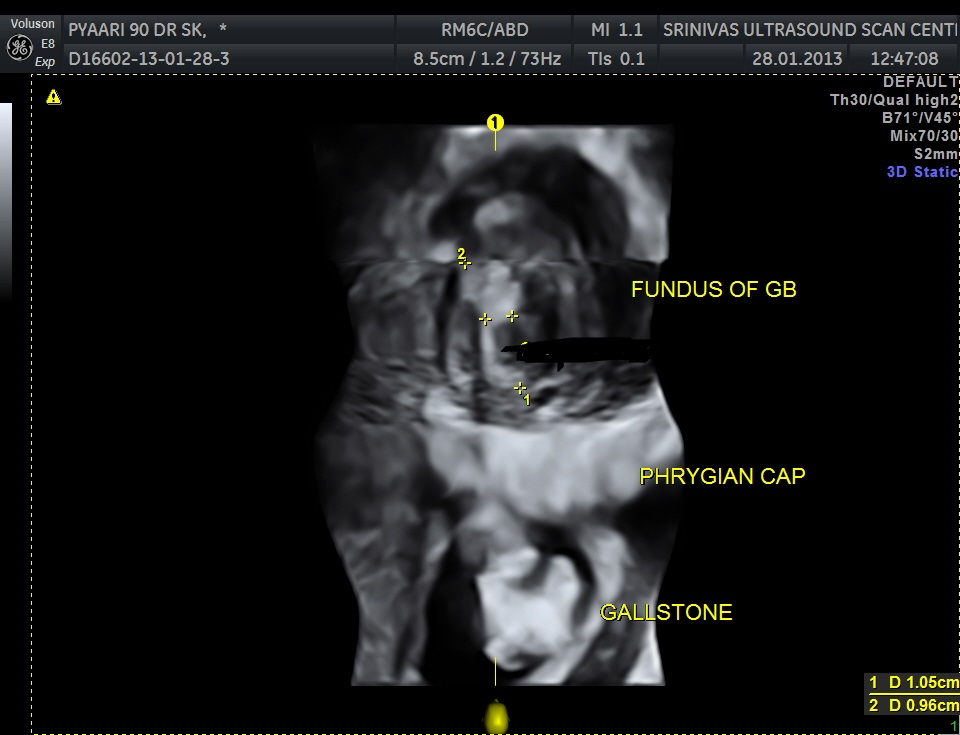

Ultrasound showed the following – Gallstone with irregular growth in the fundus of the gall bladder , above the phrygian cap.

The fundus shows irregular growth and a gallstone.